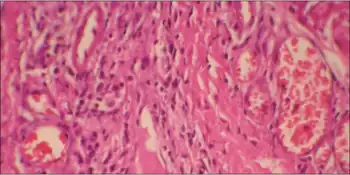

Histopathology- dermis showed intradermal localised small collections of epithelioid histiocytes

The presence of the disease can be confirmed with a genetic test. In a study of 10 infants with clinical indications of NSML prior to their first birthday, 8 (80%) patients were confirmed to have the suspected mutation. An additional patient with the suspected mutation was subsequently found to have NF1, following evaluation of the mother.[12]